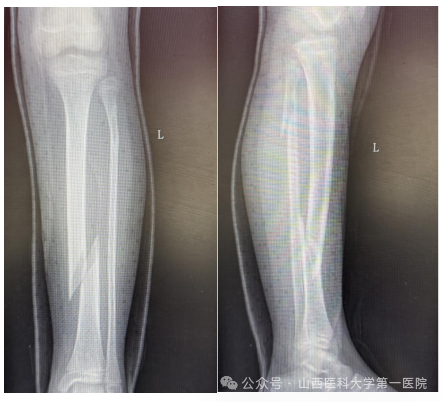

9岁女孩王某某在家中不慎滑倒后导致左小腿胫腓骨螺旋骨折,家长焦急万分,为了获得更好的治疗来到无码流出

骨科门诊,杨自权主任详细评估患者病情后收入病房继续治疗。

儿童胫腓骨骨折多因外伤导致,因儿童骨膜厚、愈合快、塑性能力强,因此微创治疗可减少手术创伤、降低并发症。但王某某为左侧胫腓骨螺旋骨折,骨折断端移位大、稳定性差,若行微创手术复位无疑增加了手术难度。杨自权主任团队分析病情后,考虑患者仅为9岁女孩,最后计划使用闭合复位儿童弹性髓内钉(ESIN)内固定术,微创手术瘢痕小,在保留美观的同时尽可能减少对儿童骨骼生长发育的影响。